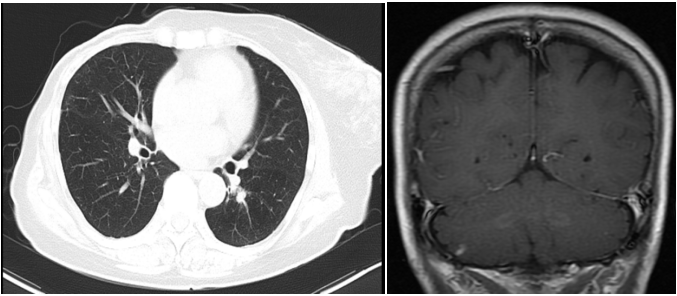

④三线治疗:曲妥珠单抗(汉曲优) 300mg Q3W+吡咯替尼 320mg QD+唑来膦酸4mg Q3M,并予以局部区域放疗。维持治疗至2022.03.31出现新发左肺转移灶及右侧小脑转移灶。行支气管镜检查,并取左肺下叶背段支气管开口见新生物活检,病理提示:(左肺结节)乳腺癌转移,Ki-67(20%,+),ER(-),PR(-),HER2(3+)。右侧小脑异常信号,1.2cm(图5),考虑转移。疗效评价PD,PFS 16个月。

图5. 2022.03左肺及右侧小脑影像图

两个疗程后评估:左肺下叶转移灶较前缩小,1.1cm;右侧小脑转移灶较前缩小,0.8cm(图6)。疗效评价 PR,继续维持该方案。

图6. 2022.05左肺及右侧小脑影像图